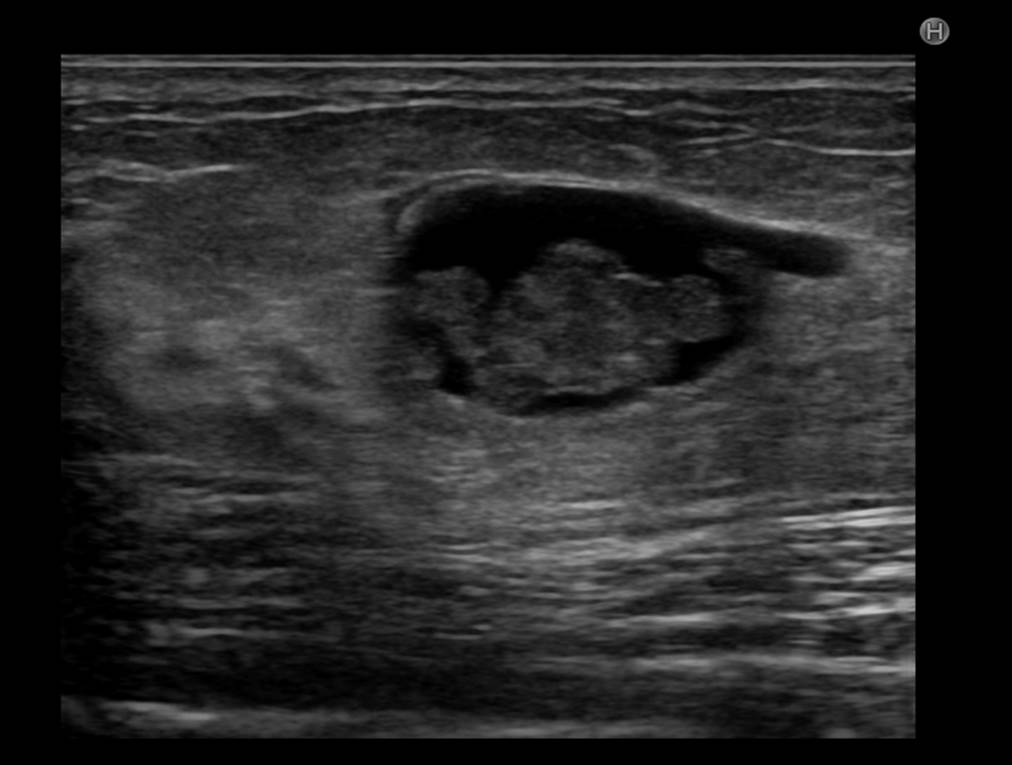

30代の女性ですが、約1年前の脂肪豊胸後の違和感で悩まれ、当院のエコー検査を受けて頂きました。